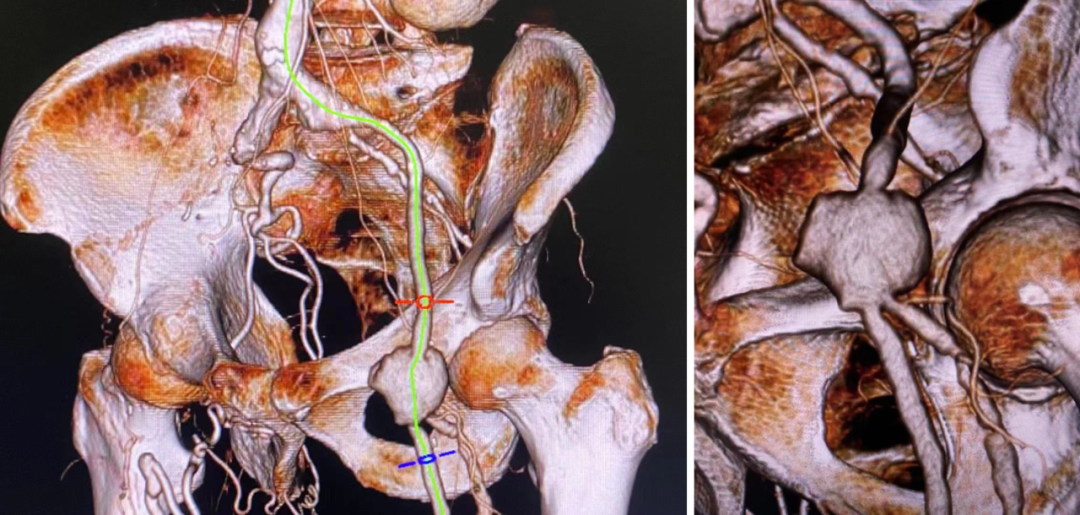

股总动脉假性动脉